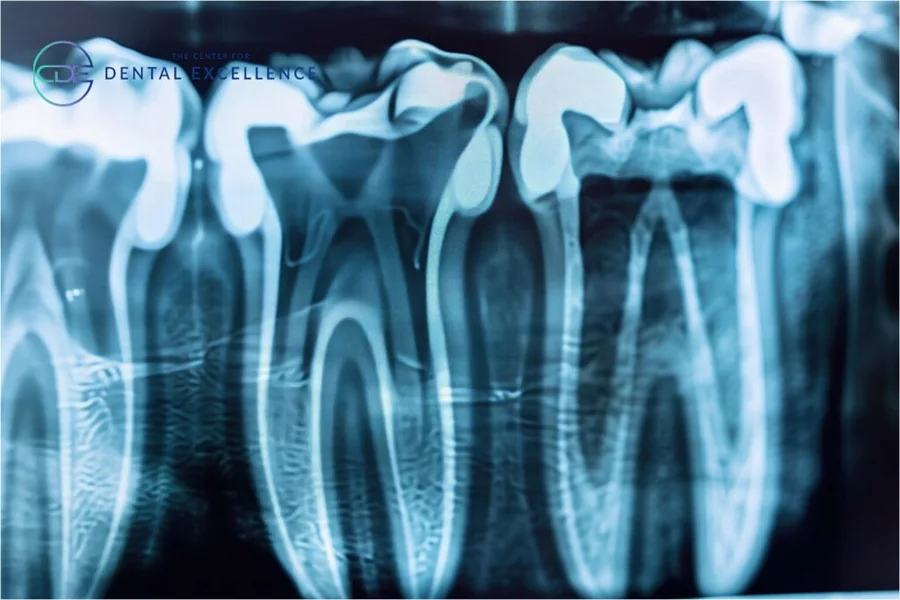

- Periapical X-rays: These focus on a few teeth from root to crown. Dentists use them to check for issues at the root or surrounding bone.

- Panoramic X-rays: These capture the whole mouth in one image. Dentists use them to see the entire jaw structure, sinus areas, and more.